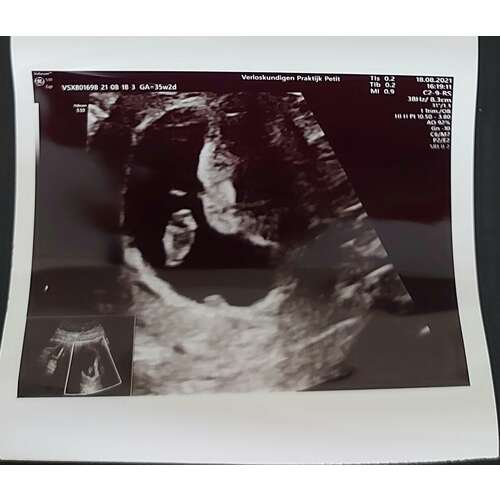

Mijn echo, dacht 7+5 te zijn maar de metingen kwamen overeen met 9+1 🥰